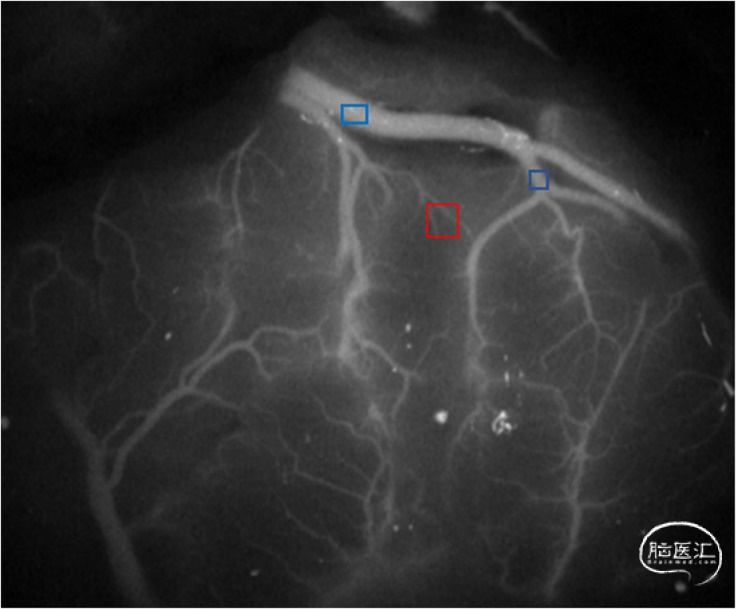

烟雾病(MMD)是一种病因不明的罕见慢性缺血性脑血管疾病,其特征是颈内动脉末端逐渐狭窄或闭塞,并在其周围形成异常血管网。这种异常的血管网十分脆弱,可能破裂、出血或导致一过性脑缺血。直接血运重建,如颞浅动脉和大脑中动脉(STA-MCA)之间的吻合,可显著降低脑出血和脑缺血的风险。MMD搭桥手术的一个危险并发症——脑过度灌注综合征(CHS)可导致严重头痛、失语、癫痫发作、局灶性神经功能缺损,甚至颅内出血。尽管这些患者的最终结果大多良好,但因为对高灌注的处理与对缺血的处理是相互矛盾的,因此,术后CHS的早期预测变得尤为重要。许多研究已经证实了搭桥手术后的血流动力学变化,这种血流动力学功能障碍似乎是CHS的预兆。目前,绝大多数通过ICG-FLOW800视频血管造影预测MMD术后CHS的研究都将感兴趣区(ROI)的选择放在手术吻合的MCA和周围其他较粗的血管上。在本研究中,我们将ROI选择目标转移到了微血管。我们将受体动脉周围小范围内的血管末端分支称为“小区域微血管”(SRMV)(图1)。我们使用ICG-FLOW800视频血管造影评估搭桥手术前后吻合口周围MCA和SRMV的血流动力学变化,验证在MMD直接血流动力学重建后,SRMV的血流动力学变化是否可用作CHS的预测指标,并计算和比较MCA和SRMV分别预测CHS的诊断准确性。

图1:两种ROI之间的区别。红色方框代表的ROI是SRMV,蓝色方框代表的ROI是MCA。